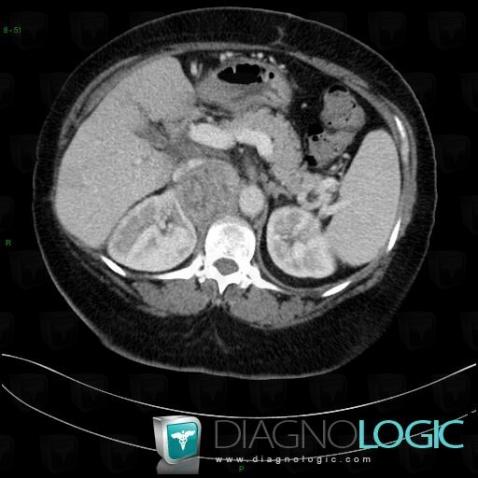

Adrenocortical carcinoma, Retroperitoneum, Adrenal glands, CT

Here is the specific information in the key image above:

- Diagnosis Adrenocortical carcinoma, Location(s) Adrenal glands, with gamuts Unilateral adrenal massRetroperitoneum, with gamuts Lesion in the perinephric space